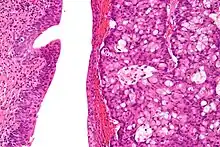

| Micrograph of urachal carcinoma (right of image) and non-malignant urothelium (left of image). H&E stain. | |